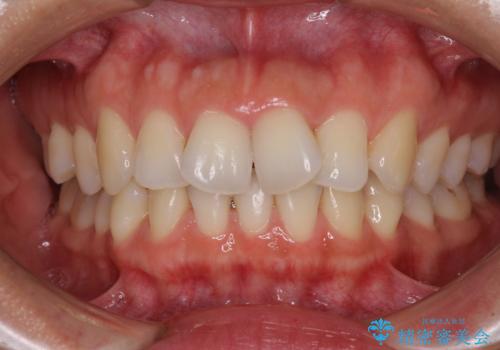

[ 前歯のねじれ・がたつき ] マウスピース矯正

![[ 前歯のねじれ・がたつき ] マウスピース矯正の症例 治療前](https://seimitsushinbi.jp/wp/wp-content/uploads/2024/02/4007c6479f6bce11863dcdd32ed5e39b-500x350.jpg?v=1708502552)

![[ 前歯のねじれ・がたつき ] マウスピース矯正の症例 治療後](https://seimitsushinbi.jp/wp/wp-content/uploads/2024/02/e7a01485e4f4dd0da04705fde4cc34cc-500x350.jpg?v=1708502585)

インビザライン モニター治療 前歯のねじれをまっすぐに